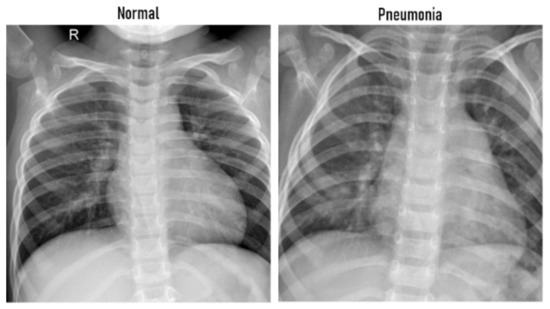

Our focus here is to evaluate the developed hybrid framework with some challenging pneumonia and COVID-19 datasets. The first application is related to COVID-19 detection. For this purpose, we considered the available dataset in [39,40] (https:https://github.com/ieee8023/covid-chestxray-dataset, accessed on 20 January 2021). This dataset contains 542 chest X-ray (CXR) images. A subset of 434 CXR images are positive for COVID-19 and the rest are normal cases. We also conduct our experiments to recognize pneumonia infections from CXR images. To achieve this purpose, we consider the publicly repository “Kaggle” (www.kaggle.com/paultimothymooney/chest-xray-pneumonia, accessed on 20 January 2021). It contains 5856 images divided into Pneumonia and Normal categories. There are 1583 normal images and 4273 pneumonia cases. An example of both normal and abnormal images from this dataset is given in Figure 2.

Figure 2.

Examples of Chest X-Rays images. (Left) Normal patient, (Right) patient with pneumonia.